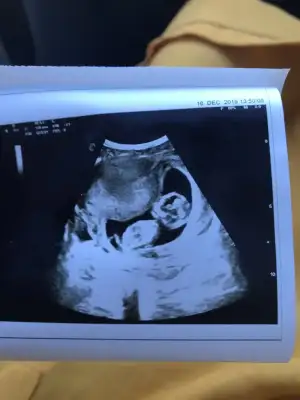

Sizce bana kız gibi geldi arkadaşlar tahminleri alalım:anneadayı:

Eklentiler

• 0ECABA96-7800-45A3-B34E-E6A90A9D5C9A.webp

0ECABA96-7800-45A3-B34E-E6A90A9D5C9A.webp

27,9 KB · Görüntüleme: 102